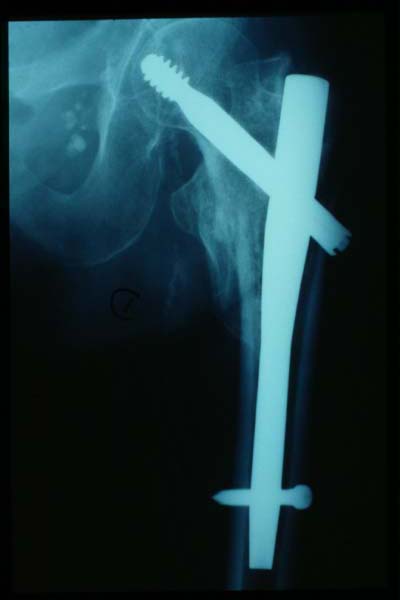

Fractura intertrocantérea de fémur, osteosíntesis

Fractura de fémur, osteosíntesis

osteosíntesis fractura fémur